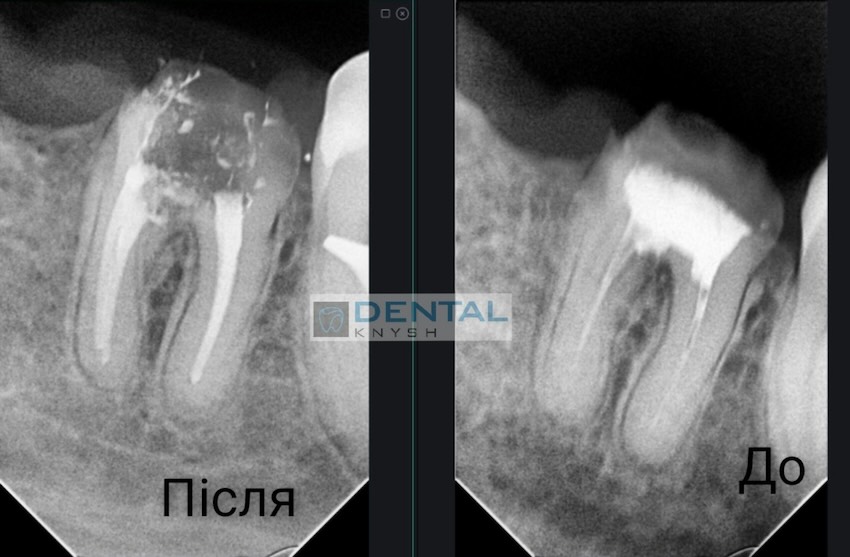

Лікар-ендодонтист Вадим Петриченко спеціалізується на лікуванні зубних каналів під мікроскопом.

Фото звіти

Більше фото звітів можна подивитися на сторінці Лікування зубів під мікроскопом